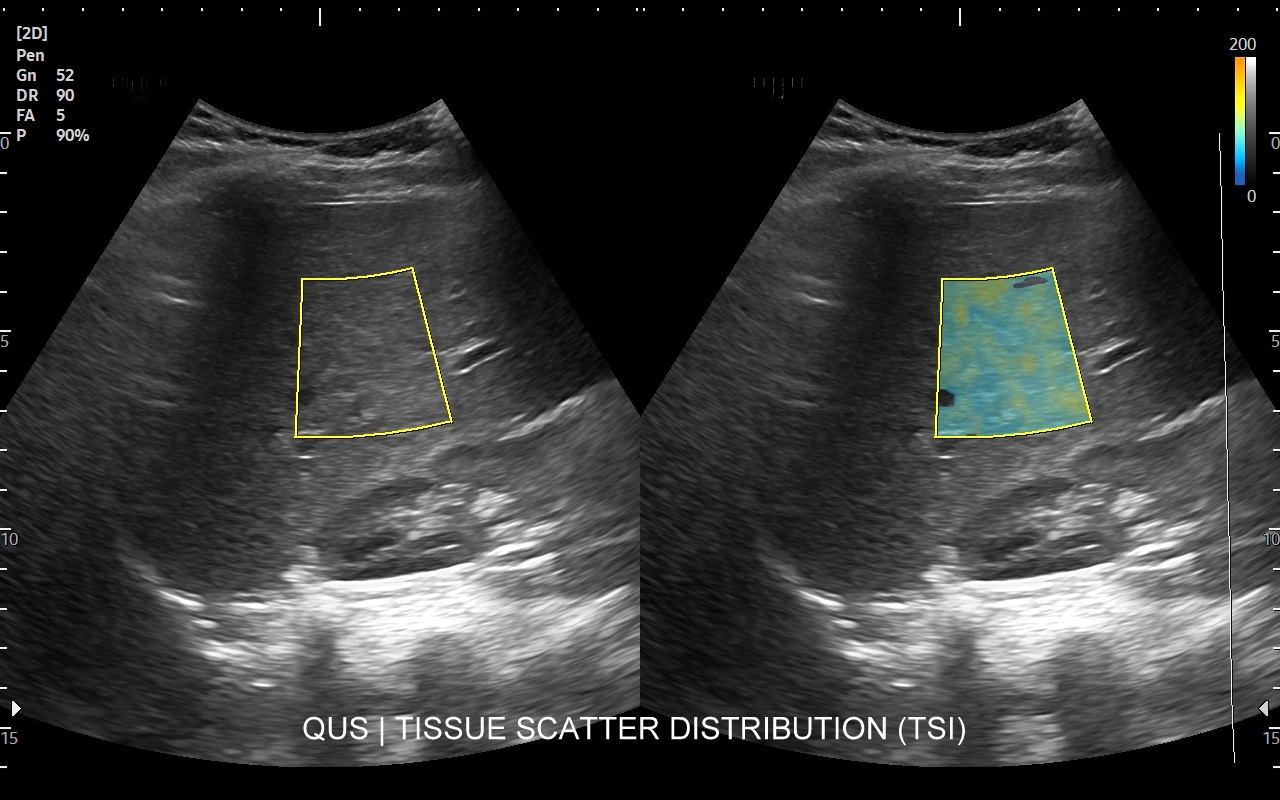

Badanie multiparametryczne MPUS jamy brzusznej

Rozwinięciem standardowego badania USG jamy brzusznej jest badanie multiparametryczne MPUS (ang. multiparametric ultrasound), w ramach którego wykorzystuje się różnorodne, nowoczesne modalności sonograficzne, takie jak tryby mikrounaczynienia MVI, B-flow, elastografię, ilościową ocenę stłuszczenia wątroby QUS, czy tryb Dopplera spektralnego, a to wszystko w celu uzyskania dodatkowej oceny funkcjonalnej i biologicznej struktur, narządów oraz tkanek jamy brzusznej. Obrazowanie MPUS niejednokrotnie poprawia także wizualną ocenę narządów wewnętrznych, czego przykładem jest zastosowanie trybu MVI w ramach bezkontrastowej angiografii sonograficznej naczyń oraz w ocenie guzów nerek. Klasycznymi i najczęstszymi zastosowaniami badania MPUS są jednakże funkcjonalna ocena wątroby w kierunku stłuszczenia, zwłóknienia, zapalenia i nadciśnienia wrotnego, a także ocena żywotności i funkcji nerek.